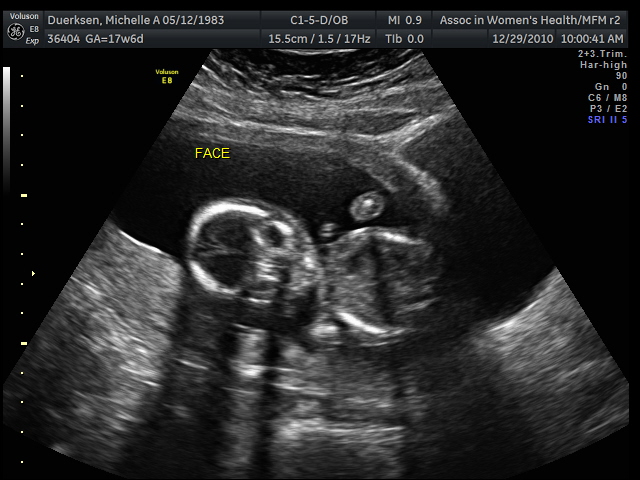

Then here are some pictures:

This first picture is always creepy. They always look like aliens looking at you. If you can make it out, her head is on the left and she is lying on her side. The little round thing towards the top is her hand with the bigger round thing without eye sockets is her tummy.